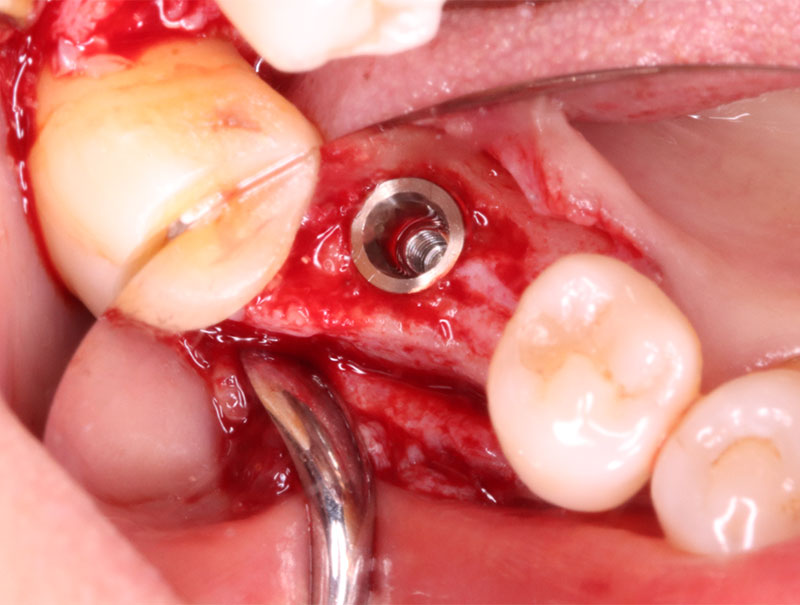

インプラント埋入手術

インプラントの埋入に関しては1回法で行いました。抜歯した部位の骨はしっかりと治癒していました。インプラント埋入後はヒーリングキャップを装着しました。手術時は特に大きな問題はなく無事に手術が終了しました。インプラントの露出を避けるためにも骨幅が少しでも広いところに埋入するために理想的な位置よりは少し後ろになっています。